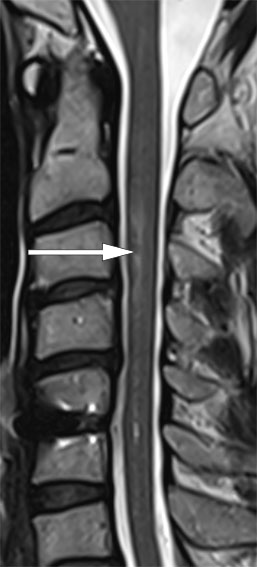

MR-undersøkelsen av hjernen viste funn forenlig med et lite, ferskt infarkt i venstre cerebellarhemisfære. Intramedullært var det nå tilkommet et mer distinkt, økt T2-signal i nivå C2–C4 (figur 1), der aksialt diffusjonsopptak viste restriktiv diffusjon innad i områder med økt T2-signal, som hadde overvekt mot venstre side (figur 2).